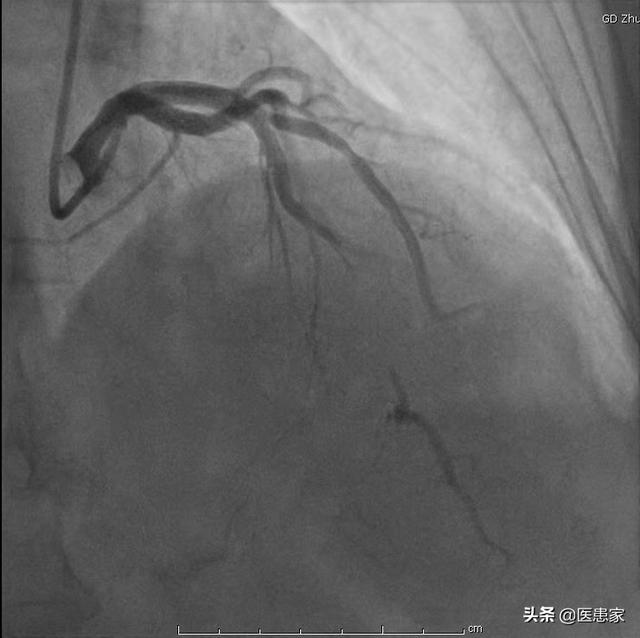

1) La coronarographie est en effet l'examen de référence pour le diagnostic de la maladie coronarienne. Il s'agit d'un examen dynamique qui permet d'identifier clairement l'emplacement des lésions sténosantes dans les différentes branches des artères coronaires et d'estimer leur étendue ainsi que l'irrigation sanguine de l'ensemble du vaisseau. Cependant, il s'agit d'un examen invasif, qui doit être réalisé par l'artère fémorale ou l'artère radiale, et le coût relatif de l'examen est plus élevé, de sorte que certains patients ne sont pas aptes à subir cet examen.

La coronarographie est en effet un examen fiable et très précis, mais elle présente aussi des inconvénients : si le vaisseau est endommagé, il faut injecter davantage de produit de contraste et la stimulation de l'artère coronaire par le fil-guide peut entraîner un risque accru de vasospasme dans l'artère coronaire.

Tout d'abord, il faut préciser que la coronarographie n'est qu'un test, un test important pour évaluer la gravité de la maladie coronarienne, le traitement de la maladie coronarienne, l'effet du traitement de la maladie coronarienne et pour déterminer si la maladie coronarienne est présente. Ainsi, pour de nombreux patients chez qui on a diagnostiqué une maladie coronarienne, afin de clarifier l'effet du traitement de la maladie coronarienne et d'évaluer la gravité de la maladie coronarienne, nous devons souvent choisir d'examiner l'angiographie coronarienne afin d'évaluer l'état de la maladie et de guider le traitement.

La coronarographie est l'une des méthodes de référence pour confirmer le diagnostic de maladie coronarienne et joue un rôle très important dans la détermination du degré de sténose des artères coronaires. Pour les patients atteints d'une maladie coronarienne due à l'athérosclérose des artères coronaires, dans les conditions médicales actuelles, il n'y a pas de remède efficace, un traitement à long terme est nécessaire, afin de stabiliser et de contrôler l'état et de réduire l'apparition de complications, nous devons prêter attention à la surveillance des changements de l'état et à l'examen régulier en même temps que le traitement régulier, et adhérer à l'examen régulier du contrôle de l'état et à l'élaboration d'un programme individualisé a un rôle irremplaçable, afin que les patients atteints d'une maladie coronarienne puissent bénéficier d'un traitement de qualité. Les patients atteints d'une maladie coronarienne doivent faire l'objet d'un examen régulier.

La maladie coronarienne fait principalement référence à la cardiopathie coronarienne athéroscléreuse, qui est une maladie cardiaque due à l'athérosclérose des artères coronaires, qui entraîne un rétrécissement ou une occlusion des artères coronaires, avec pour conséquence l'ischémie, l'hypoxie et la nécrose des cellules du muscle cardiaque. Pour diagnostiquer une maladie coronarienne, il est nécessaire de combiner les symptômes cliniques, les tests de laboratoire, l'électrocardiogramme, la tomodensitométrie coronarienne, la coronarographie et d'autres examens complets.